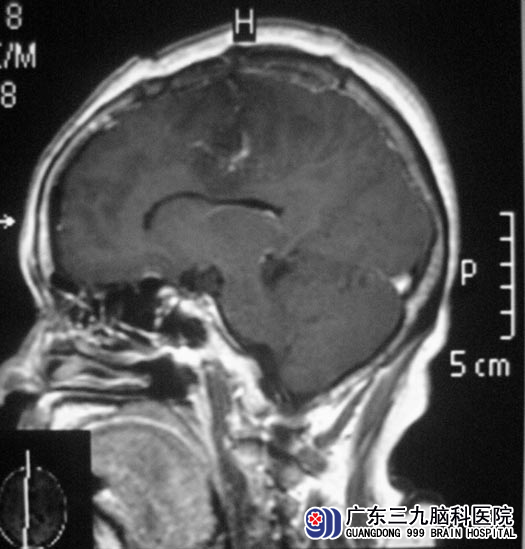

刘姨,67岁,半年前出现左侧肢体活动不利,精细活动差,当地医院头颅MR检查提示右侧镰旁占位性病变,大小约5.0cm×5.0cm。综合神经外科 鲁明主任从影像资料分析:肿瘤位于右侧功能区,主要表现为功能区压迫症状,术中功能区的保护将成为手术的难点。

5月18日,由鲁明主任主刀,在显微镜下行肿瘤切除手术,术中沿大脑镰探查可见灰白色肿瘤,呈颗粒状,血供丰富,肿瘤质中,包膜完整,与脑组织粘连,先分离肿瘤基底部,然后逐步切除肿瘤。在显微镜下全切除肿瘤,术中出血少,功能保护完好,术后恢复顺利,未出现功能损害症状,痊愈出院。术后病理诊断为:过渡型脑膜瘤,WHO I级。